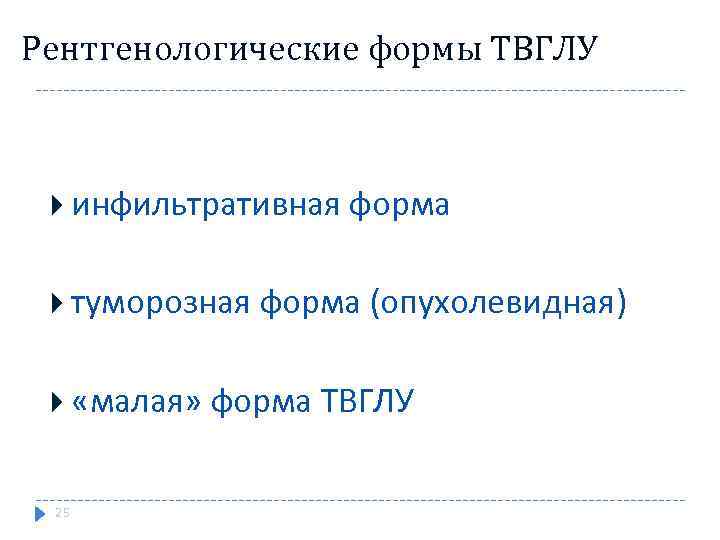

Рентгенологические формы ТВГЛУ инфильтративная форма туморозная форма (опухолевидная) «малая» форма ТВГЛУ 25

Рентгенологические формы ТВГЛУ инфильтративная форма туморозная форма (опухолевидная) «малая» форма ТВГЛУ 25